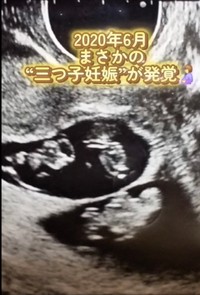

地元では珍しいコウノトリを発見!「願掛けで待ち受けにしたら」→1カ月後に三つ子が!……夫婦で感動「やっぱり奇跡だったんだね」